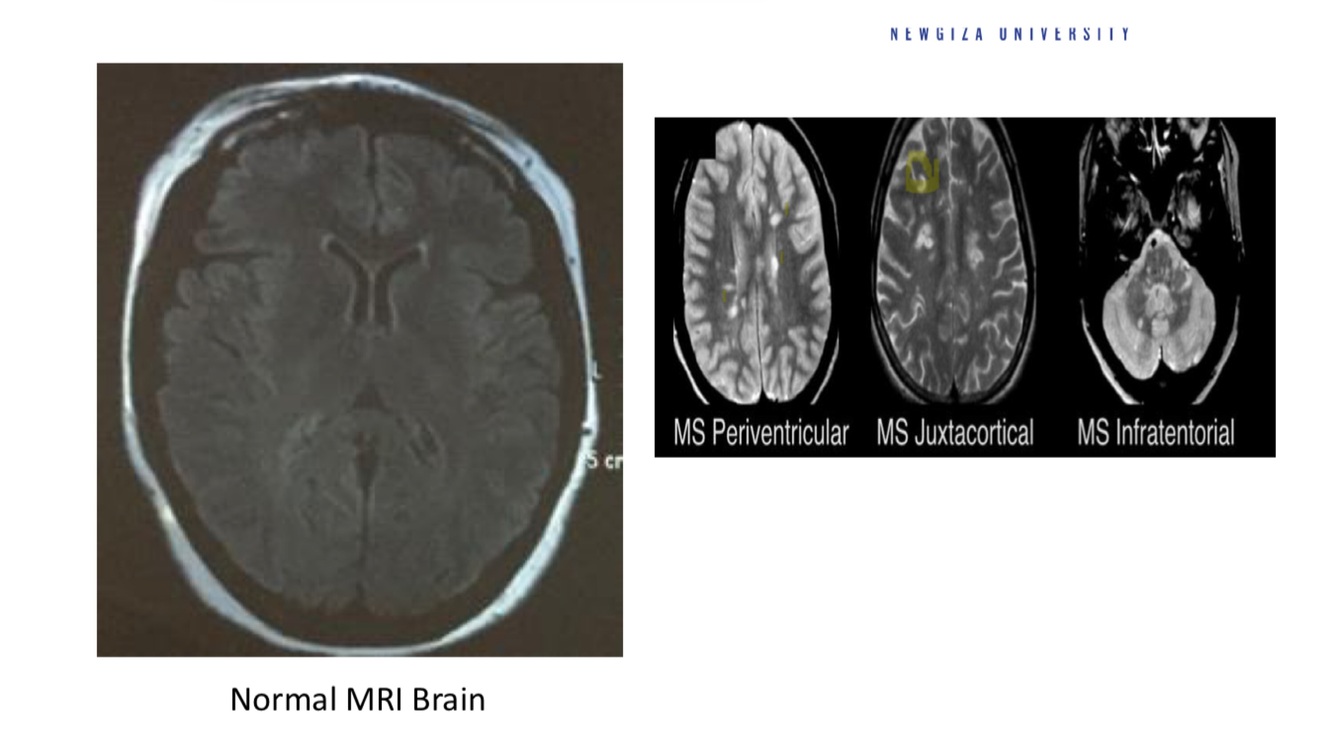

Diagnose

what do you see